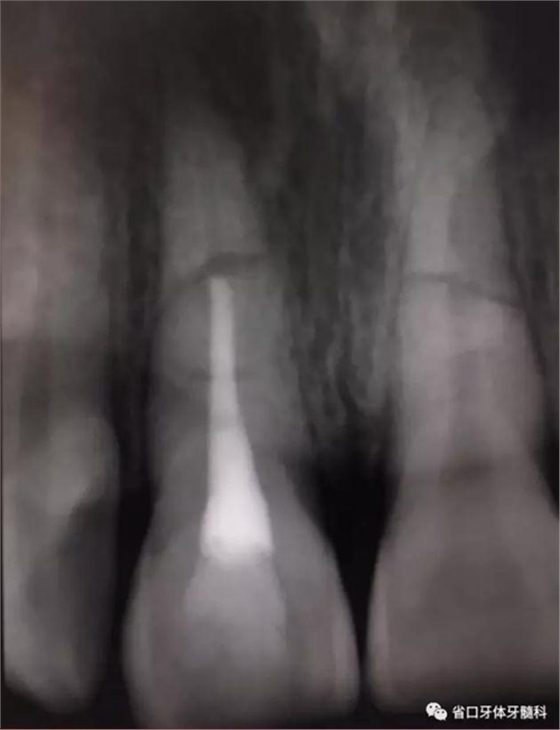

圖6 斷端MTA封閉術(shù)后

處理:11橡皮障隔濕,顯微鏡下開髓,揭髓室頂,K銼疏通根管,拔髓,測長度(到根折斷端處)17mm,顯微鏡下鎳鈦預(yù)備根管,按工作長度預(yù)備根管至60#,沖洗根管,吸干,顯微鏡下MTA斷端封閉,髓腔內(nèi)放置半飽和蒸餾水棉球一個,玻璃離子臨時充填。

圖7 熱牙膠根充片